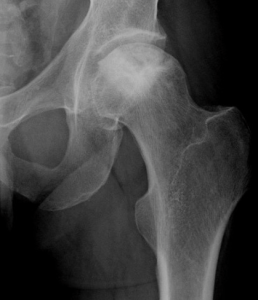

L’ostéonécrose de la tête fémorale est une affection sérieuse de l’articulation de la hanche, pouvant résulter d’un traumatisme ou survenir de manière primitive. Le